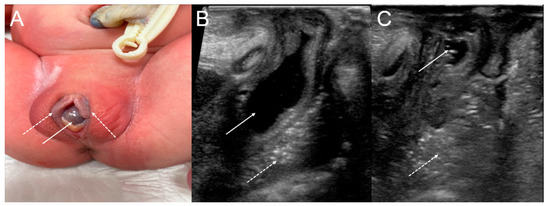

Perineal inspection revealed a normal anus, a normally situated urethral meatus, a bulge at the vaginal introitus, and a cystic mass protruding between the labia minora (Figure 2A). The remainder of the physical examination was unremarkable.

Figure 2.

(A) The cystic bulging mass (arrow) arising from the right vaginal wall between the labia minora (dotted arrow) after birth. (B) On the initial ultrasound with a perineal approach, a fluid-filled cystic lesion (arrow) in the right pelvic cavity was noted anterior to the rectum (dotted arrow). (C) After aspiration, the previously observed cystic lesion collapsed (arrow).

When the baby was eight days old, an ultrasound-guided needle aspiration of the cystic mass protruding between the labia minora, not the vaginal septum, was performed, and yellow serous fluid was aspirated. The collapsed cystic lesion was observed after the needle aspiration, and its appearance was suggestive of a Gartner duct cyst diagnosis (Figure 2B,C).